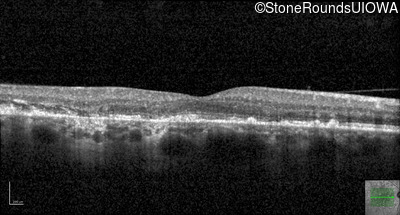

Pattern Dystrophy (IIC)

Age at visit: 49 years

This 49 year old man was first told he had a fundus abnormality on a routine eye exam at age 34. Ten years later he noticed some distortion just superior to fixation.

Pattern Dystrophy PRPH2 Gln239Stop CAG>TAG   AD